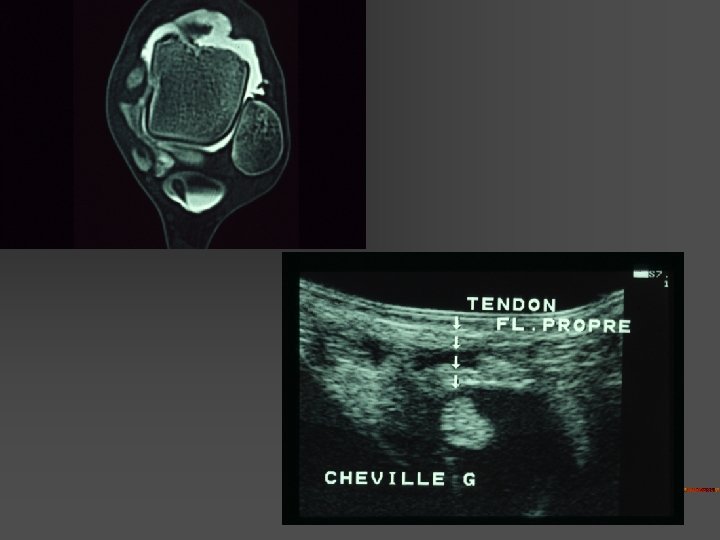

SCP microtraumatique : Lésions n n n Inflammation récessus capsulo-ligamentaires postérieurs Arthrose talo-crurale ou sous-talienne postérieure # de stress tibio-talienne postérieure Lésion ostéo-chondrale dôme talien postérieur Tendinopathie Fléchisseur Propre de l’Hallux (TS > fissures IT)

SCP : Diagnostics différentiels Avec flexion plantaire douloureuse - Tendinopathies du Long Fléchisseur de l’Hallux . Situation : gouttière du processus post. Du talus ( tunnel ostéo-fibreux non extensible) . Facteur favorisant : jonction MT basse - jonction N = niv. Art. tibio-talienne - jonction basse = niv. Talus ou face médiale calca. n (néanmoins anomalies le plus svt asymptomatiques) - Lésion ostéochondrale dôme talus ou du pilon tibial (séq. T , kyste , …)